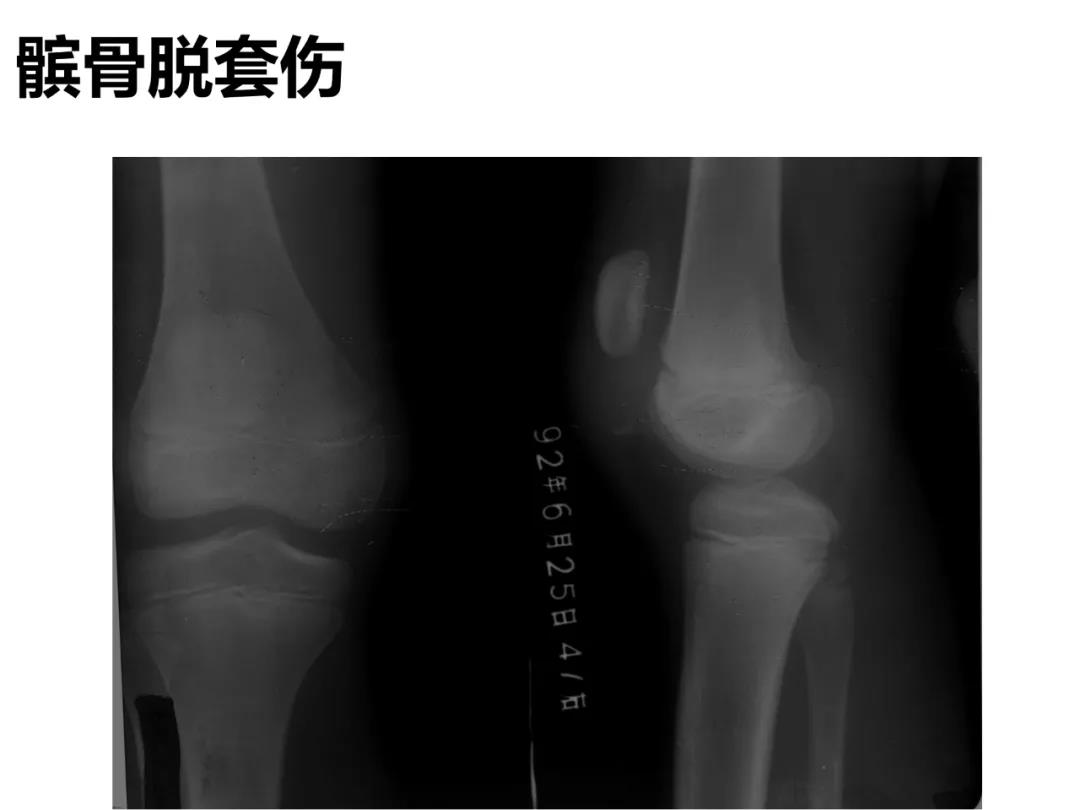

小儿骨科X线片汇总,临床读片宝典!